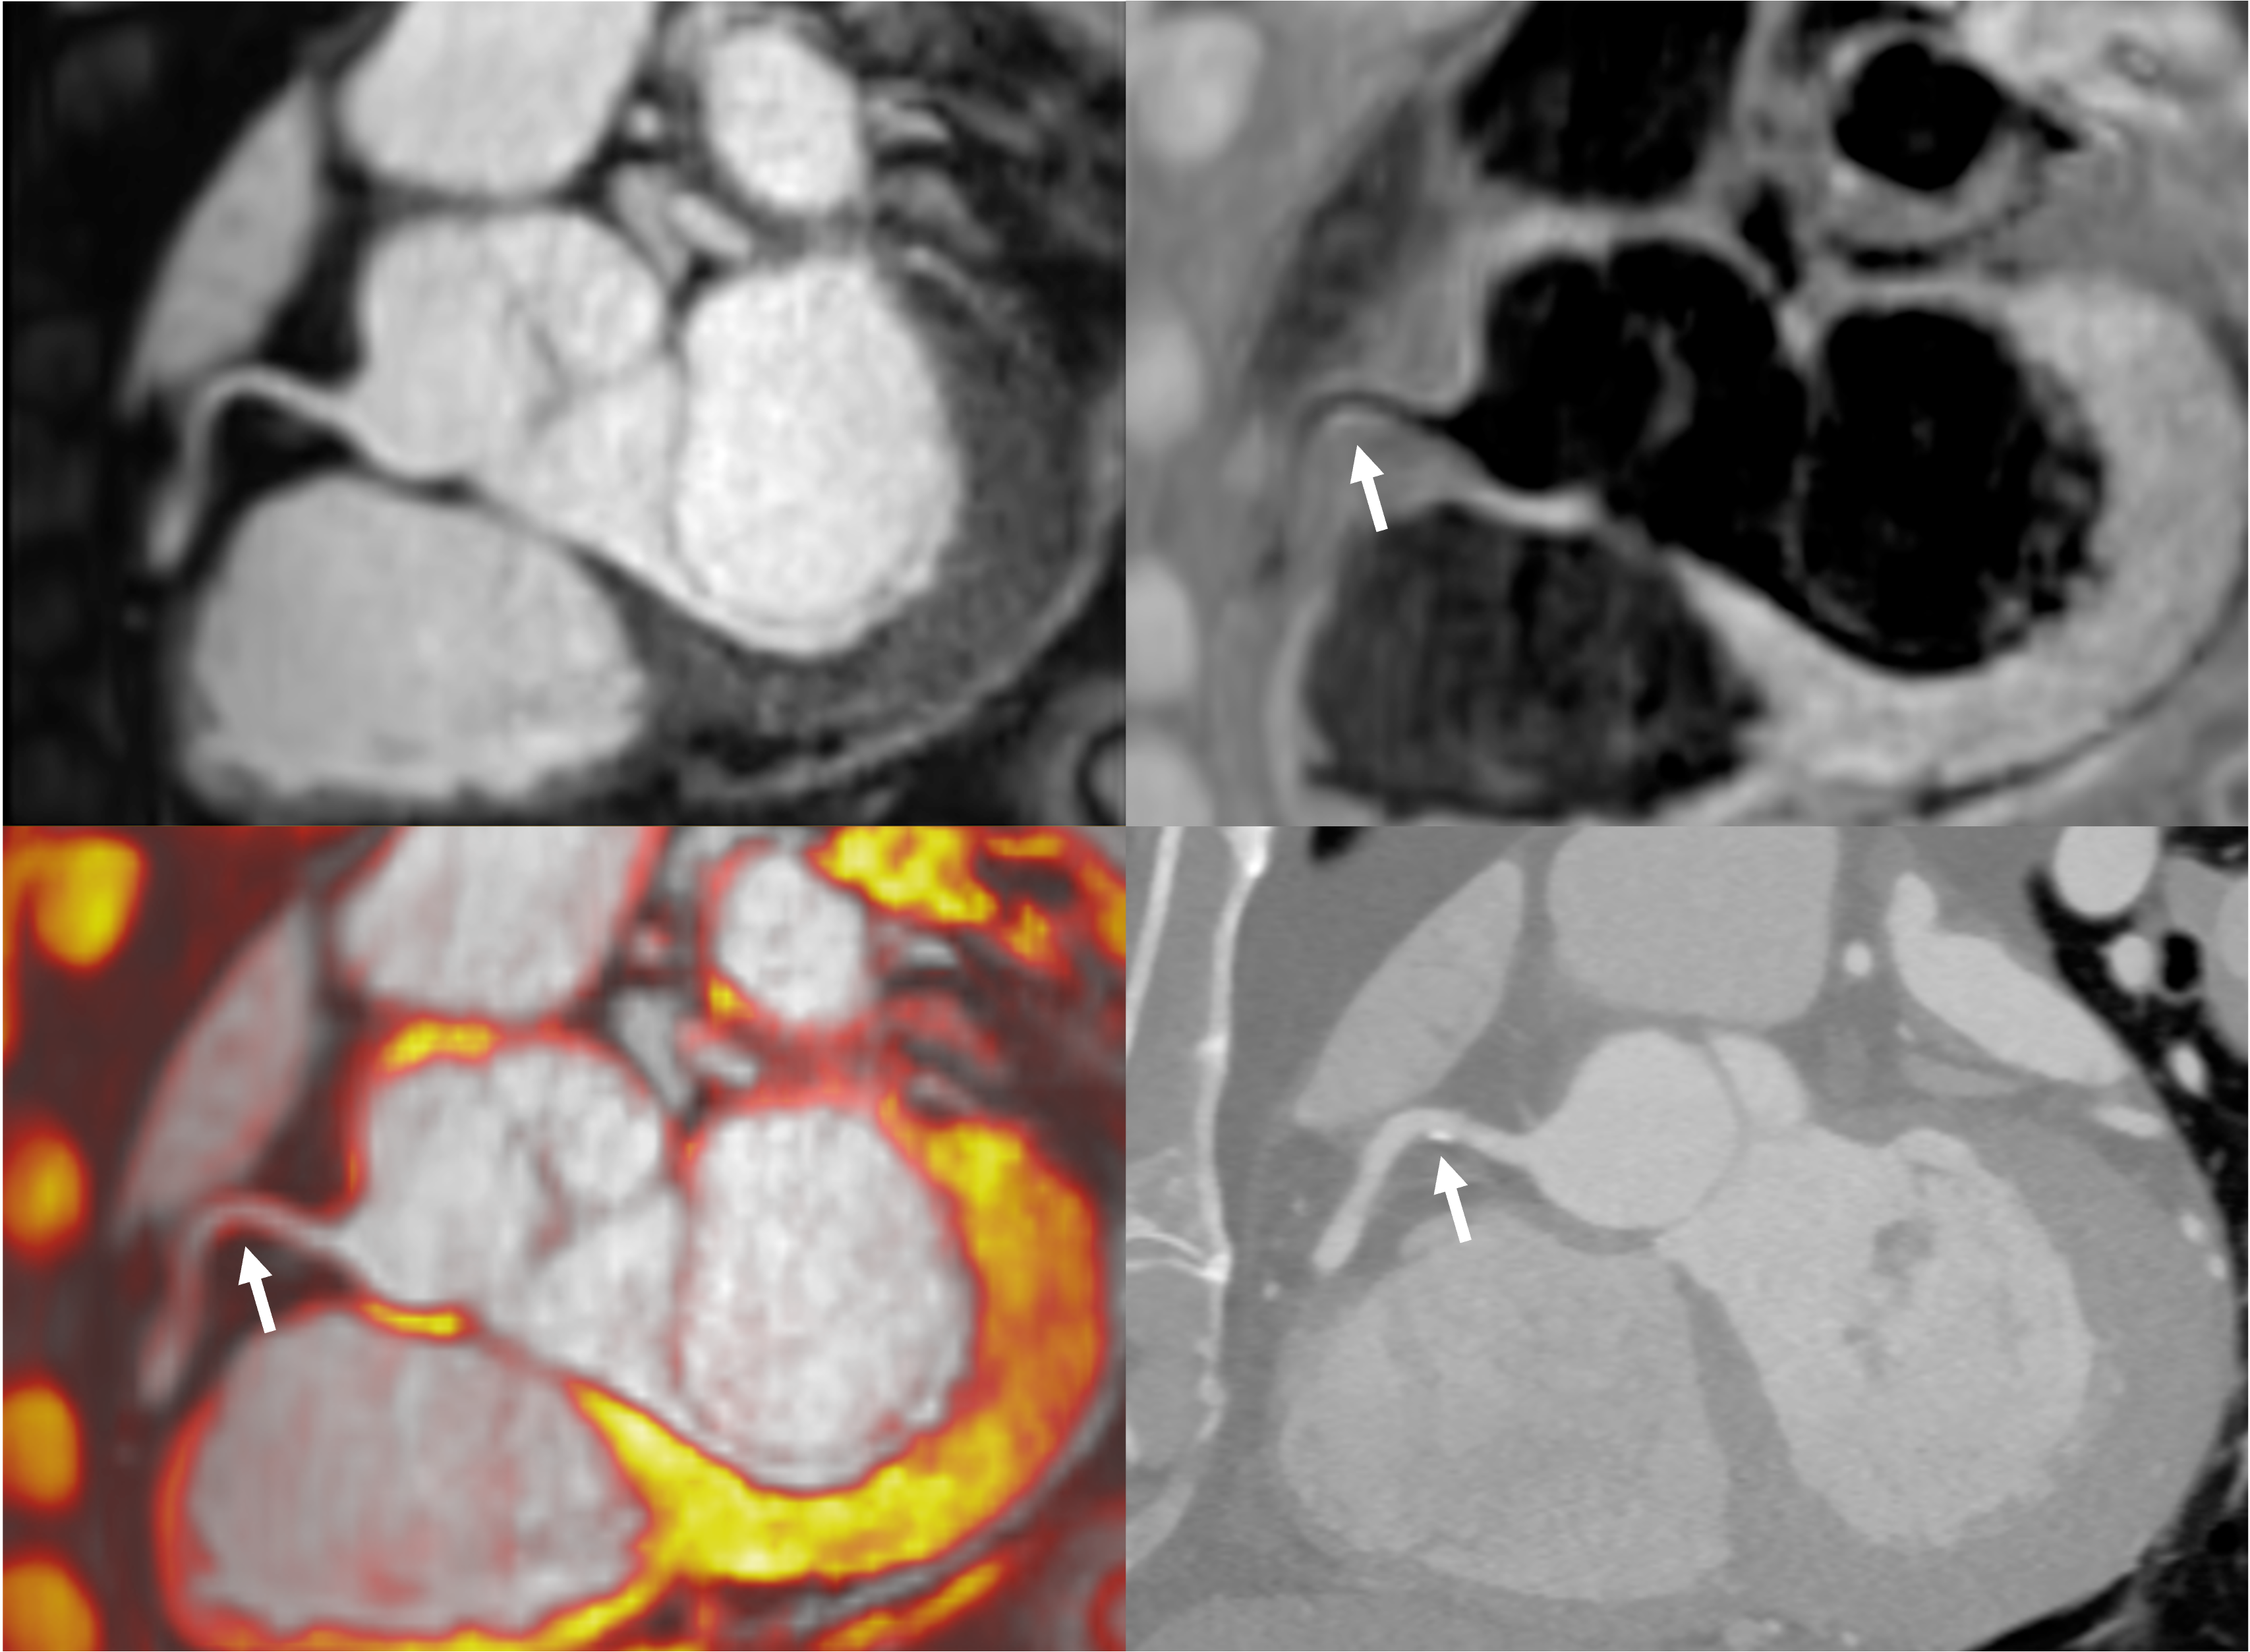

Figure 2. Plaque visualisation in the proximal RCA using iT2prep-BOOST and CTCA. Top left: BOOST bright-blood image; Top right: BOOST black-blood image; Bottom left: fusion image of bright- and black-blood BOOST; Bottom right: corresponding CTCA image. White arrows indicate the location of an atherosclerotic plaque in the proximal RCA, which appears hyperintense on the black-blood image and corresponds to a partially calcified lesion on CTCA.